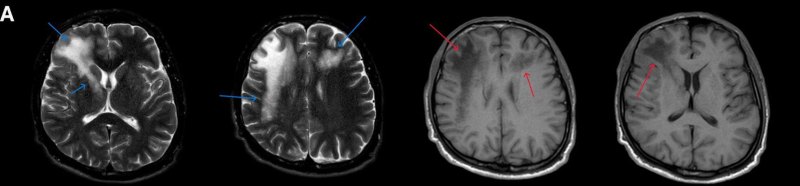

1. A) Aksiyel T2A görüntülerde bilateral sağda belirgin frontoparietal subkortikal ve derin periventriküler beyaz cevherde subkortikal U fiberleri boyunca yerleşimli sinyal artımları (oklar) izlendi.  Tarifli alanlar aksiyel T1A serilerde hipointens görünümde (oklar) izlendi.

2. B) Aksiyel diffüzyon ağırlıklı serilerde bilateral sağda belirgin frontoparietal subkortikal ve derin periventriküler beyaz cevherde periferal DAG hiperintens ADC hipointens, hafif diffüzyon kısıtlaması (oklar) eşlik etmektedir. IVKM sonrası kesitlerde tarifli alanlarda belirgin kontrast tutulumu (oklar) izlenmedi.

1. PML’de MRG bulguları genellikle multifokal, asimetrik periventriküler ve subkortikal beyaz cevher tutulumu şeklindedir. Subkortikal U-fiberleri sıklıkla tutulur, özellikle parietooksipital bölgelerde belirgin lezyon eğilimi vardır.

2. T1 ağırlıklı görüntülerde tutulan bölgeler hipointens, T2A’da ise hiperintens izlenir. Ana lezyon çevresinde çok sayıda noktasal (milkyway) sinyal artımları görülebilir. Ayrıca spleniumu çaprazlayan parietooksipital sinyal değişiklikleri (barbell bulgusu) ve dentat nukleusu koruyarak serebellar beyaz cevher tutulumu (shrimp bulgusu) da tanımlanmıştır.

3. Kontrastlı incelemelerde genellikle kontrast tutulumu izlenmez. Diffüzyon görüntülemede özellikle lezyonun ilerleyen periferik alanlarında yamalar halinde diffüzyon kısıtlılığı izlenir. MR spektroskopide NAA azalması, laktat varlığı ve artmış kolin ve lipid düzeyleri görülür. MR perfüzyonda ise lezyonların ilerleyen kenarında perfüzyon artışı saptanabilir.

4. Bizim hastamızda bilinen HIV enfeksiyonu mevcuttu ve yapılan kraniyal MR görüntülemede multifokal, asimetrik, periventriküler ve subkortikal beyaz cevherde yerleşimli, kitle etkisi göstermeyen ve kontrastlanmayan lezyonlar izlendi. Lezyonların subkortikal U-fiberleri tutması ve özellikle parieto-oksipital bölgelerde belirgin olması nedeniyle ön planda PML düşünüldü. Histopatolojik tetkik ile PML tanısı doğrulandı.